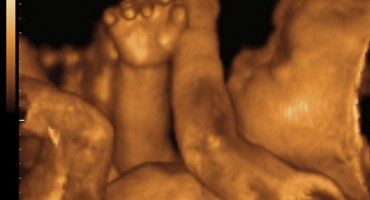

Video s 4D ultrazvuka koji je objavila Facebook stranica Meddy Bear pretvorila je nerođenu bebu u pravu internetsku zvijezdu. Iako nije jasno kad i gdje je video snimljen i tko su roditelje ove bebe,…

U ovom ćete ultrazvučnom snimku vidjeti kako beba radi gimnastiku u vodi. Izvor: cafe.hr

Svakom budućem roditelju posebno je iskustvo vidjeti svoju bebu na ultrazvuku, a pogotovo kad beba napravi nešto zanimljivo. Bebe u trbuhu spavaju, zijevaju, neke i sišu palac, ali…